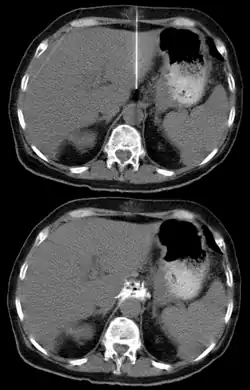

Liczne przerzuty raka trzustki do wątroby

Przerzut raka trzustki do trzonu kręgu

Przerzut do sklepienia czaszki

Inwazyjny rak trzustki najprawdopodobniej powstaje na bazie stosunkowo dobrze zróżnicowanych nieinwazyjnych zmian. Najczęstszą taką zmianą prekursorową jest śródnabłonkowa neoplazja trzustkowa (pancreatic intraepithelial neoplasia, PanIN)[141], a rzadziej wewnątrzprzewodowe brodawkowate nowotwory śluzowe (intraductal papillary mucinous neoplasm, IPMN) i śluzowe nowotwory torbielowate (mucinous cystic neoplasm, MCN)[131]. Śródnabłonkowa neoplazja trzustkowa może nabywać kolejne mutacje cytogenetyczne, co koreluje z progresją do raka[141]. Prawdopodobnie musi minąć 12 lat, zanim śródnabłonkowa neoplazja trzustkowa ulegnie przemianie do raka inwazyjnego, i kolejne 6,5 roku, nim nowotwór nabędzie zdolność do wytworzenia przerzutów. Po około 2,5 roku zwykle dochodzi do dalszych mutacji i progresji choroby do zgonu, zatem mija około 21 lat od pierwszej mutacji genetycznej do śmierci chorego[131][142].

Przerzuty drogą krwionośną pojawiają się głównie w wątrobie i płucach, następnie w nadnerczach, nerkach, kościach, mózgu i skórze[113]. Najczęstszą lokalizacją przerzutów jest wątroba i przerzuty w tej lokalizacji są stwierdzane w 60% przypadków przerzutów odległych[152]. Klinicznie w zaawansowanej chorobie nowotworowej obserwuje się postępujące pogorszenie stanu ogólnego, nasilenie bólu i spadek masy ciała, prowadzi to do kacheksji i ostatecznie do zgonu[153].